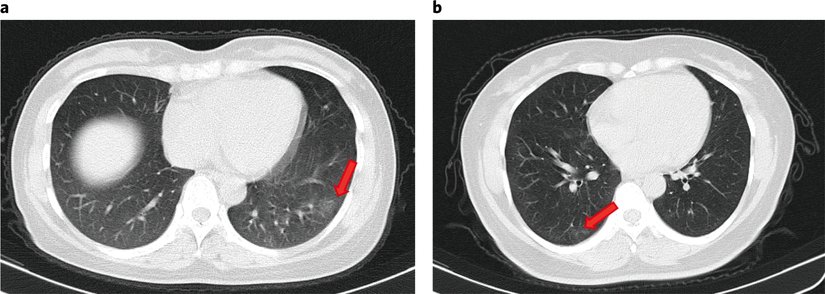

Başvuru üzerine, Toraks BT (bilgisayarlı göğüs tomografisi) taramaları 16 bireyde (16/37, %43.2) herhangi bir anormallik göstermez iken; 11 asemptomatik bireyde (11/37, % 29,7) fokal zemin cam opasiteleri (akciğerde buzlu cam görünümü) ve 10 kişide (10/37, % 27,0) şerit gölgeler ve/veya yaygın konsolidasyon (alveollerde hava boşluklarının yerini püy, sıvı veya hücrelerin alması) gösterdi. Alveollerin iltihaplanması ve şişmesi durumunda çekilen akciğer grafilerinde buzlu cam görüntüsü şeklinde anomaliler olur. Alveollerin iltihaplanmasına neden olan birçok faktör ve hastalık vardır.

5 kişi hastaneye başvurduktan sonraki 5 gün içinde göğüs BT'de fokal zemin cam opasiteleri veya şerit gölgeler geliştirdi. Kritik semptomatik hastalarda görülen tipik değişiklikler olan plevral efüzyon (akciğerde su toplanması), hava bronkogram (bronşlarda dallanan tübüler patolojik görünüm) belirtisi veya genişlemiş lenf nodu yoktu. Asemptomatik bireylerin % 66.7'sinde (14/21) bir akciğer lobunda sınırlı anormal radyolojik bulgu saptanırken, her iki akciğerde % 33.3'ünde (7/21) anormallik vardı.